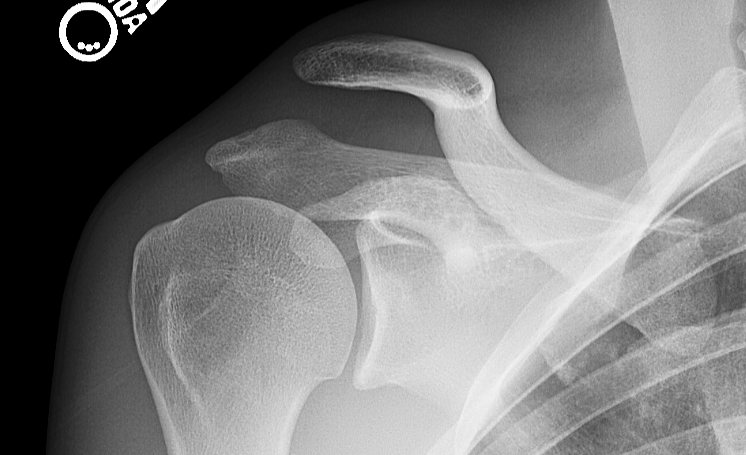

High-grade AC joint injury (shoulder separation). Note the superior displacement of the clavicle relative to the acromion, indicating that both the AC and CC ligaments are ruptured.

X-rays of high-grade AC joint injury (shoulder separation) before and after surgical repair.